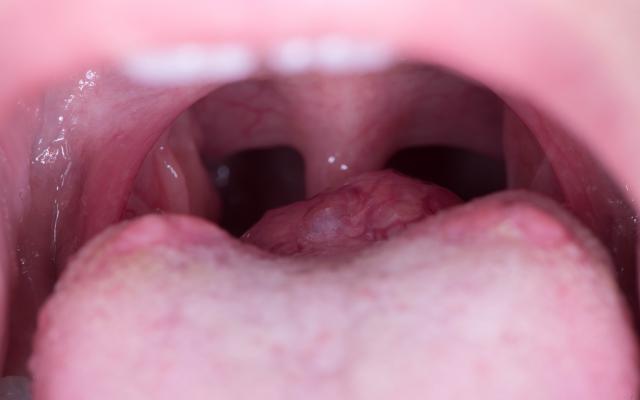

Een meisje met een zwelling op de tongbasis

Een zwelling op de tongbasis.

Een 8-jarig meisje kwam bij de kinderarts vanwege een zwelling achter op de tong. Ze had de zwelling een aantal weken eerder voor het eerst opgemerkt. Ze voelde de zwelling tijdens slikken zonder dat zij daar slikproblemen van ondervond. Er was geen sprake van dyspneu. In de voorgeschiedenis was de uitslag van de neonatale hielprikscreening bij haar positief voor congenitale hypothyreoïdie. Kort na de geboorte was een schildklierscintigrafie verricht. Het scintigram liet alleen ter plaatse van de tongbasis een gebied zien met geringe accumulatie van radioactiviteit, passend bij een aanlegstoornis van de schildklier met ectopisch linguaal schildklierweefsel. De diagnose…